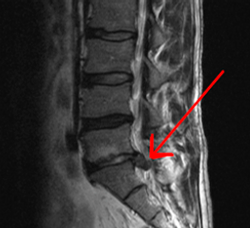

Una hernia discal se produce cuando el contenido del disco intervertebral L5-S1 se sale del disco y se introduce en el canal lumbar, en ocasiones el material discal puede comprimir y afectar a las estructuras nerviosas. cuando tenemos una hernia L5-S1 se pueden afectar la raíz L5 a su salida por el agujero que se forma entre ambas vértebras, y la raíz S1 antes de que salga de la columna. Si la hernia es muy grande también se pueden afectar las raíces sacras y producirse un síndrome de cola de caballo.

DIAGNÓSTICO

Electomiografía. Se trata de una prueba que nos va a indicar que raíz o raíces están afectadas. Recuerda que una raíz puede verse afectada a distintos niveles, la raíz L5 podría estar afectada a nivel L4-L5 o L5-S1. La electromiografía consiste en situar unos electrodos por la pierna a través de los cuales vamos a pasar unas corrientes, mediremos el tiempo que tardan el estímulo eléctrico en llegar al pie y si se pierde intensidad de señal a lo largo del recorrido. En el caso de que el tiempo que tarde la señal eléctrica sea mayor o esta llegue más débil al electrodo final, podremos decir que raíz está afectada.